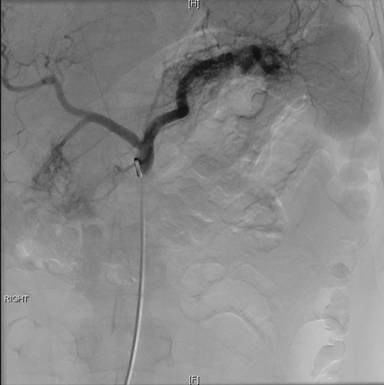

The celiac angiogram demonstrated large vascular malformations involving both the pancreatic head and tail (Figure 2). Superselective angiogram of the splenic artery demonstrated a feeding artery just 2 to 3 cm away from the splenic hilum feeding the pancreatic tail arteriovenous malformation. Superselective catheterizations of hepatic artery and gastrojejunal artery showed no significant contributions to the pancreatic head arteriovenous malformation.

Figure 2. The celiac angiogram demonstrating: two large vascular arteriovenous malformations involving both the pancreatic head (yellow arrows) and tail (white arrows). |